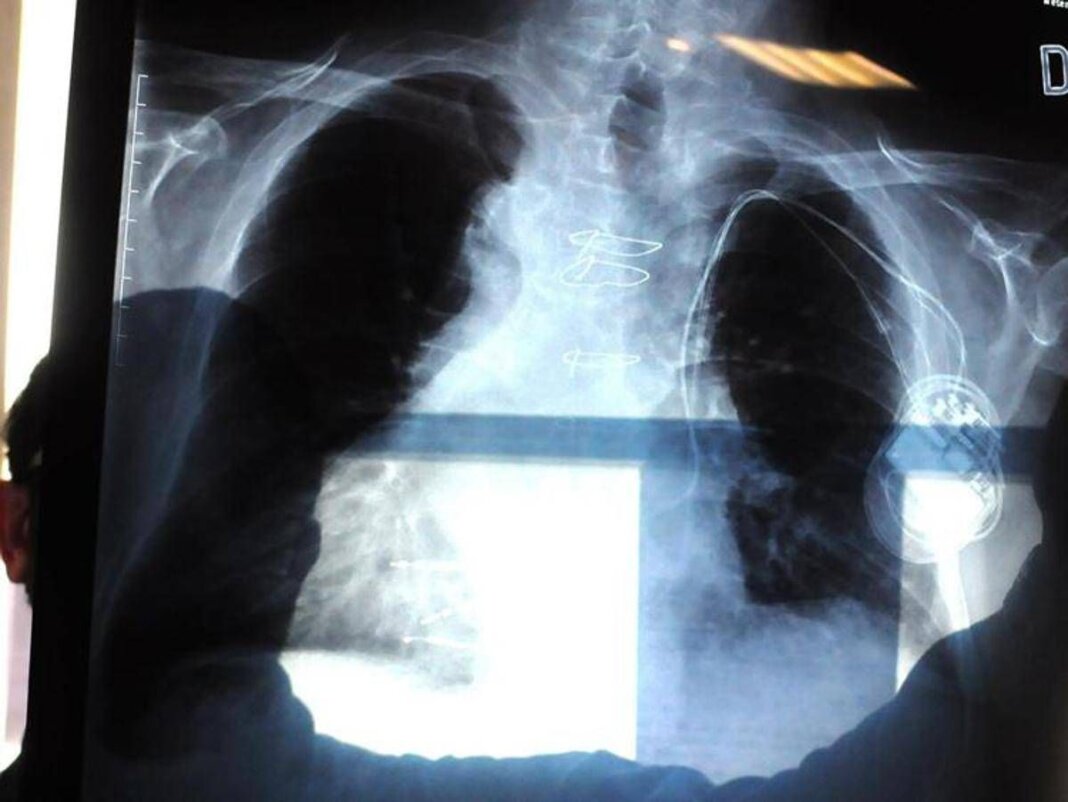

La polmonite, prosegue il presidente di Aipo, è un’infezione che “può essere localizzata in un punto particolare del polmone. L’ente patogeno più frequente in questo caso è lo pneumococco, contro il quale esiste appunto una vaccinazione. Esistono poi le polmoniti interstiziali che colpiscono il tessuto connettivo del polmone, l’area dove avviene lo scambio, per questo l’infezione può essere molto diffusa e anche bilaterale. E’ dovuta prevalentemente a virus, il Covid tra questi, come abbiamo visto durante la pandemia, e ad alcuni batteri. Altro caso abbastanza emblematico è la legionella, oppure i cosiddetti agenti intracellulari, micoplasma e clamidia”. L’intestizio, precisa Micheletto, “è il tessuto di sostegno del polmone, dove avviene il passaggio dell’ossigeno e dell’anidride carbonica nel senso contrario, tra gli alveoli e i capillari. Quando questo interstizio viene colpito, lo scambio viene notevolmente ridotto. Ma se il paziente ha la bronchite cronica o è un fumatore, questi spazi sono già compromessi. E quindi può dare casi gravi”.

Ma quali sono i segnali d’allarme che indicano una possibile polmonite? “Una polmonite si presenta prevalentemente tosse e febbre”, descrive lo pneumologo. Ma la “gravità che causa ospedalizzazione riguarda la difficoltà respiratoria, che può essere altamente rischiosa”, conclude.